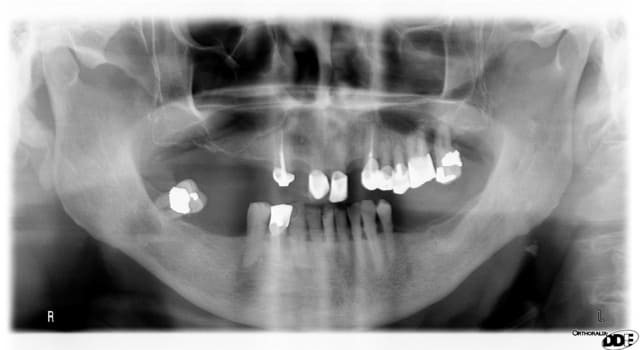

Un patient de 80 ans, ancien fumeur, en bonne santé si on excepte un diabète type 2 compensé diagnostiqué à 46 ans, âge auquel il a arrêté de fumer.

Il n'a pas vu de dentiste depuis 20 ans et vient pour faire refaire sa prothèse maxillaire. Il ne porte plus la mandibulaire depuis 10 ans ("elle était devenue gênante").

Je me pose des questions sur l'image en apical de la 47, qui est vitale et normalement mobile, insensible à la percussion.

Il n'y a pas de voussure, ni de ganglions, aucune sensibilité particulière.

Vu l'âge et le contexte..., cette image ne correspond sans doute à aucune lésion suspecte.

il faudrait palper la mandibule pour voir si tu sens une lacune à ce niveau du côté linguale.

la mandibule peut être simplement plus fine de ce côté par rapport au côté opposé tout simplement.

sinon l'hypothèse de la "glande quelconque" est possible sauf que la glande en question est la submandibulaire et par un prolongement antérieur peut "creuser" la mandibule" sur sa face interne et donner ce qu'on appelle la fameuse "lacune de stafne". La topographie et le type d'image correspondent.

quand on regarde l'otp de plus près, on remarque également une "raréfaction osseuse" du coté opposé mais qui est moins marqué.

a priori je penche pour une particularité anatomique, étant entendu que se que j'avance se base uniquement sur le petit otp fourni et le l'anamnèse rapportée.